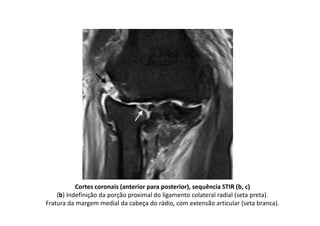

Ressonância magnética do cotovelo direito

Corte coronal, sequência T1 (a)

(a) Osteófitos marginais no côndilo umeral medial e na ulna (setas), irregularidade dos

contornos do osso subcondral do úmero, rádio e ulna

Cortes coronais (anterior para posterior), sequência STIR (b, c)

(b) Indefinição da porção proximal do ligamento colateral radial (seta preta).

Fratura da margem medial da cabeça do rádio, com extensão articular (seta branca).

c) Espessamento heterogêneo e ondulação do tendão comum dos extensores (seta).

Significativo edema dos planos gordurosos da região lateral do cotovelo.

Edema intra-muscular peri-articular

Corte sagital, sequência STIR (f)

Corpo livre intra-articular (seta).

Derrame articular